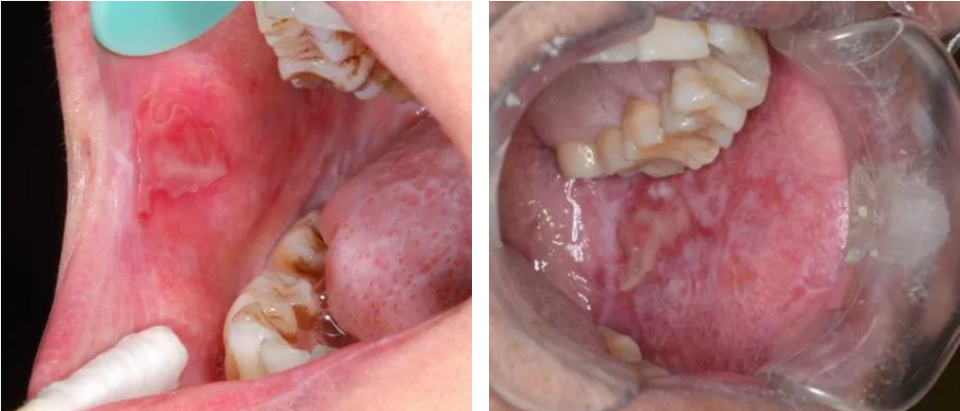

cGVHD不再单纯以移植后100天来划分,而是根据临床表现界定,最早可出现在移植后2个月2,其中45%~83%的cGVHD患者会出现口腔受累,而约20%的患者其cGVHD仅单独表现在口腔3。口腔cGVHD可累及口腔任何部位的黏膜,其特征性表现为口腔苔藓样损害——黏膜上出现网状或树枝状白色条纹4-5,外观类似植物苔藓而得名。在此基础上,病变可表现为黏膜红斑、糜烂、溃疡、假膜形成、萎缩,并伴随小唾液腺囊肿5。患者的主观症状多样,包括但不限于疼痛、口干、味觉改变以及对辛辣、酸性食物的敏感,晚期可出现张口受限6。这些表现并非孤立存在,而是共同构成了一张严重影响患者身心健康的网络。

溃疡形成及苔藓样损害(图片源自陶人川教授团队)